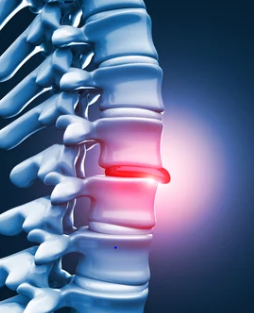

허리 디스크, 또는 추간판 탈출증은 많은 사람들이 겪는 통증의 원인 중 하나입니다. 이 상태는 척추 사이에 위치한 디스크가 손상되거나 변형되어 신경을 압박할 때 발생합니다. 허리 디스크의 원인은 다양하지만, 가장 흔한 원인은 다음과 같습니다.

허리 디스크, 또는 추간판 탈출증은 척추의 디스크가 제자리에서 벗어나 주변 신경을 압박하는 상태를 말합니다. 이로 인해 통증, 저림, 감각 이상 등 다양한 증상이 나타날 수 있습니다. 허리 디스크의 가장 흔한 증상은 허리 통증이며, 이 통증은 다리로 방사될 수도 있습니다. 또한, 디스크가 신경을 압박하면 해당 신경이 지배하는 영역에 감각 이상이나 근력 약화가 발생할 수 있습니다.

허리 디스크의 증상은 사람마다 다르게 나타나며, 일부 사람들은 아무런 증상이 없을 수도 있습니다. 하지만 일반적으로 다음과 같은 증상들이 관찰됩니다:

1. 허리 통증: 특히 오래 서 있거나 앉아 있을 때, 무거운 물건을 들었을 때 통증이 심해질 수 있습니다.

2. 다리로의 방사통: 허리에서 시작된 통증이 엉덩이, 대퇴부, 종아리, 발까지 이어질 수 있습니다.

3. 감각 이상: 디스크에 의해 압박된 신경으로 인해 저림, 찌릿함, 또는 마비감을 느낄 수 있습니다.

4. 근력 약화: 신경 압박이 오래 지속되면 해당 신경이 지배하는 근육의 힘이 약해질 수 있습니다.